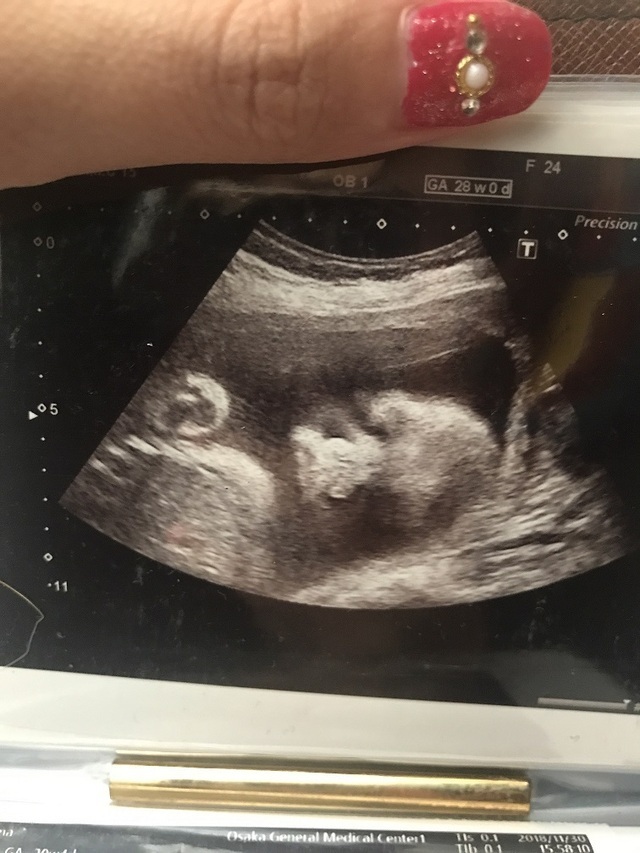

28週0日(28w0d・女の子)|yuzukichi さん(20歳)

エコー写真撮影時のエピソード:

4Dのエコー凄く楽しみにしてました!せっかくの4Dなのに手で顔を隠して寝ていて、なかなか顔を見せてくれず…(泣)

看護師さんがお腹を揺すって頑張ってくれたおかげで顔を見ることができました(笑)エイリアンみたい!って思いつつも見た瞬間キュンってして早く会いたい欲が高まりました!